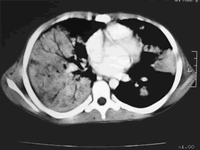

气胸、乳糜胸、双肺弥漫性病变

双侧胸腔积液、心包积液

如何阅读肺部弥漫性病变的CT片